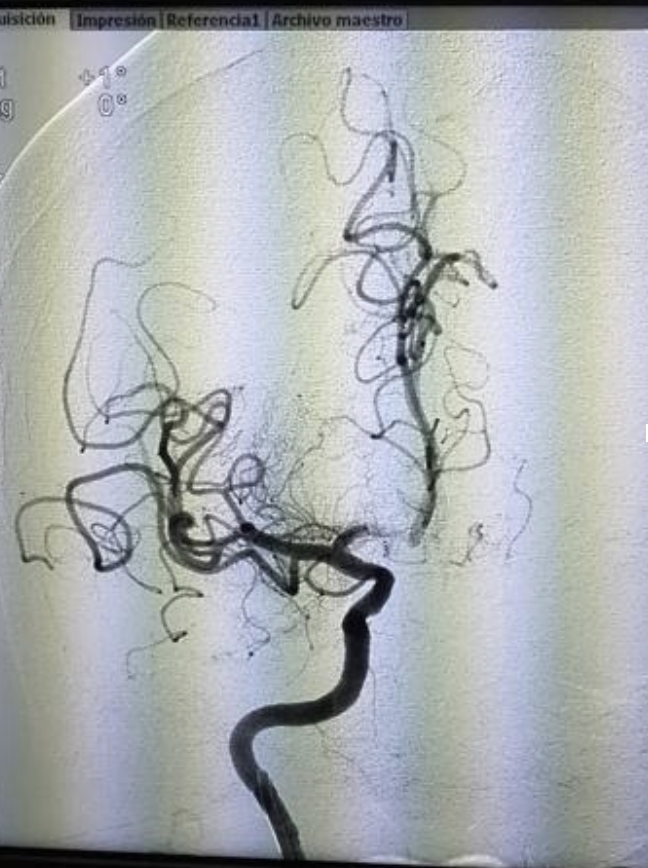

La neurocirugía endovascular es el procedimiento que seguimos los neurocirujanos para la reparación de los vasos sanguíneos, por medio de métodos minimamente invasivos. De manera más amplia consiste en un conjunto de procedimeintos para el dignóstico y tratamiento de enfermedades del sistema nervioso.

Así, la neurocirugía endovascular permite resolver eficazmente las afectaciones presentadas; se realiza por medio de la introducción de un catéter que viaja hacia el cerebro y permite llegar a la lesión para tratarla, sin necesidad de hacer una intervención quirúrgica “tradicional”, lo cual ayuda a evitar otras complicaciones y al paciente le permite una recuperación más rápida, sin necesidad de permanecer en el hospital por muchos días.